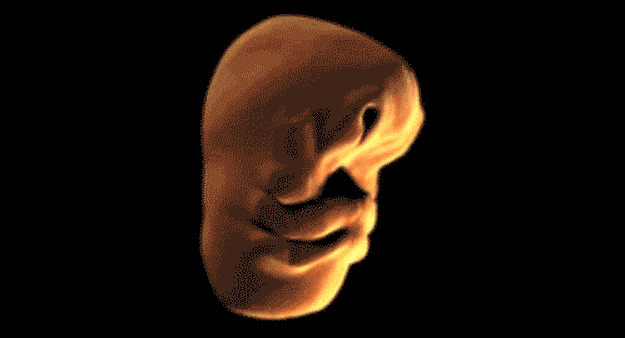

Így változik meg egy ember arca a méhben